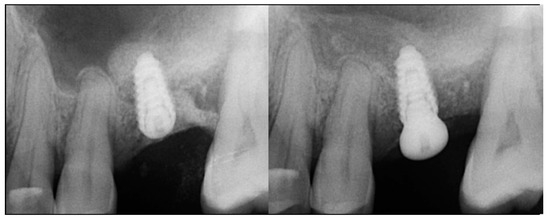

At 10 weeks post-extraction, the patient presented, and consent forms were reviewed and signed for grafting and implant treatment. Soft tissue had healed, closing the site with keratinized tissue (Figure 8, middle). A radiograph was obtained to check what available bone was present at both sites (Figure 8, right). Sufficient height was available to place an implant at the 1st molar site in conjunction with a crestal sinus augmentation, but insufficient height was present at the 2nd molar site which would require grafting to increase crestal height and later implant placement could be performed at that site.

Local anesthetic was administered, and a full thickness flap of the area was elevated. Utilizing a similar technique as outlined in case 1, the 1st molar site underwent a crestal lift and a 4.5 × 8.5 mm Anyridge (Megagen, Busan, Republic of Korea) implant was placed (Figure 9). The defect present at the 2nd molar site, resulted in a crestal height of 1.5 mm, which was insufficient for implant stability if a simultaneous crestal sinus left was performed (Figure 9, middle). Thus, grafting would need to be performed to prepare the site for later implant placement. EthOss graft material was hydrated in the syringe as previously described and placed into the defect to increase crestal height following healing (Figure 9, right).

Figure 9.

Site was reentered at 10 weeks post-extraction and an implant was placed with a crestal sinus augmentation utilizing EthOss graft material at the 1st molar site and a large defect was present at the 2nd molar site (left), with a radiograph obtained to document the implant placement at the 1st molar and grafting of the defect (middle) and following crestal grafting of the 2nd molar site (right). Green line is the measurement of the height of the bone at that point between the crest and the sinus floor.